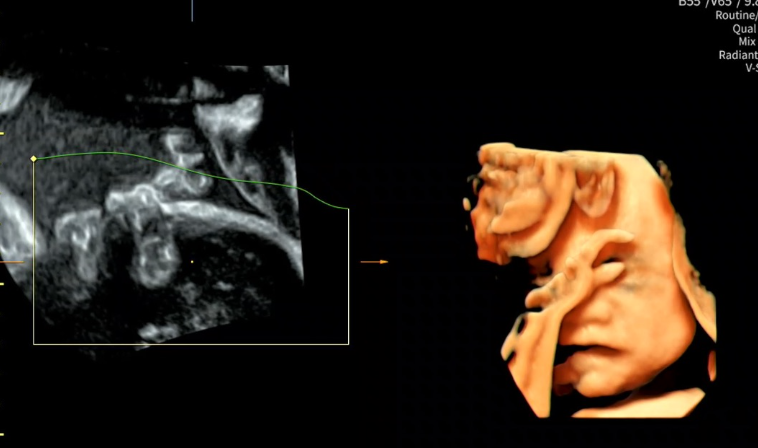

선둥이 1032g

후둥이 1135g

으로 모두 1kg 가 넘게 자랐습니다.

쌍둥이들 간에 성장 차이는 9%

오늘도 의사 선생님은 9% 정도면 차이 나는것도 아니라고 안심하라고 하셔서 다행이였어요.

물도 많이 마셔서 양수도 충분했고,

지금은 아이들 머리가 모두 밑으로 내려와있어서 자연분만도 가능하다고 하셨어요!